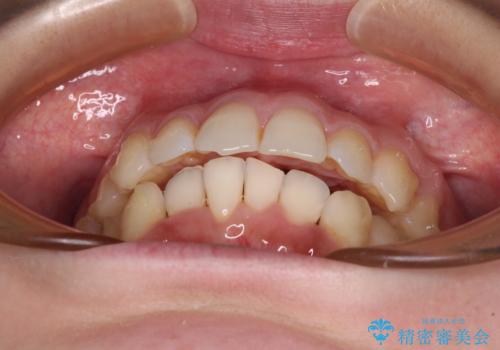

- 前歯のデコボコで前方に出ていることを気にして来院された患者様です。

上顎前歯が捻れて前方に飛び出しており、下顎前歯もそれに沿うようにデコボコとなっていました。

IPR(歯と歯の間を削る処置)によりスペースを獲得して上下顎前歯のデコボコを改善し、飛び出している前歯が引っ込むように設定し、インビザラインにて矯正治療を行うこととしました。

左右ともに、上顎第二大臼歯が欠損しており、下顎の第二大臼歯が十分に咬み合う歯がない状態のため、放置しておくと下顎の奥歯が挺出してくる可能性があります。

安定した咬み合わせを維持するためにも、将来的に上左右にインプラント補綴が必要となります。